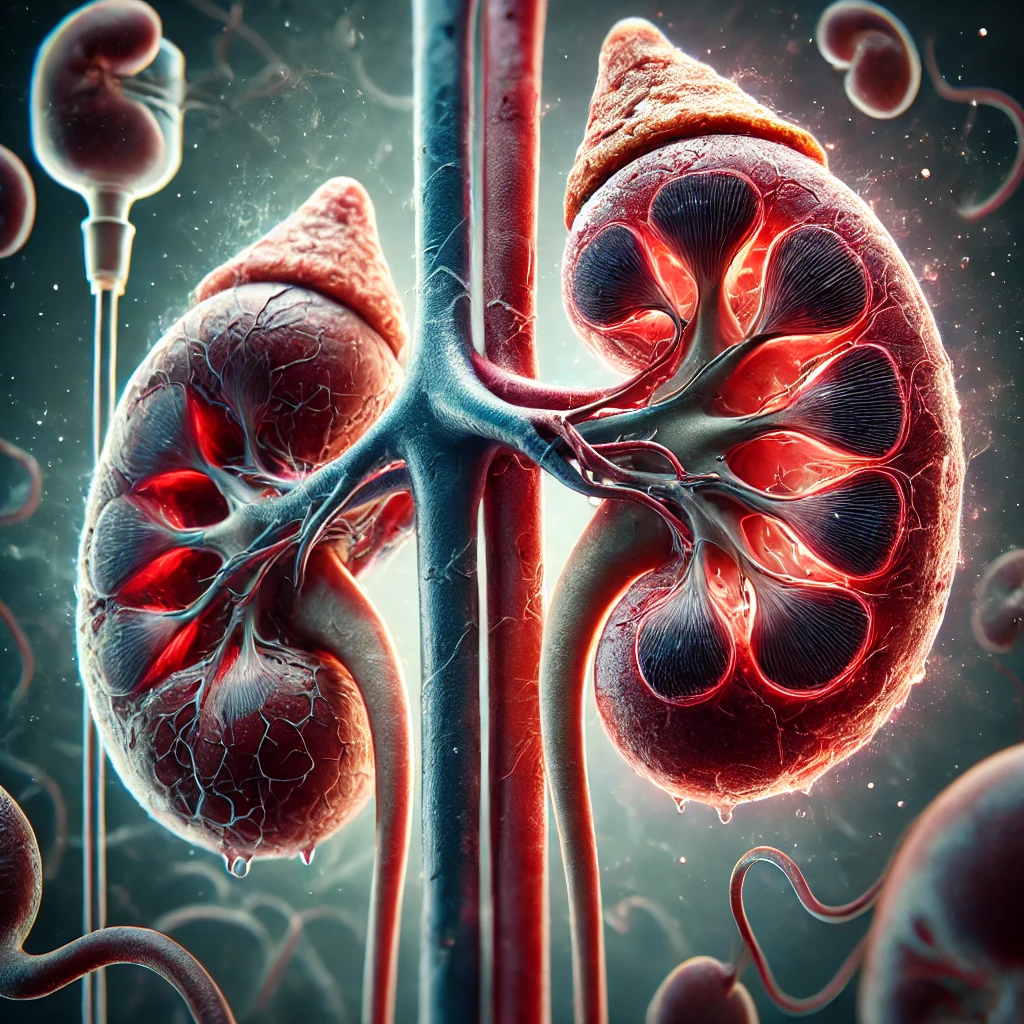

Débito urinário como marcador precoce de lesão renal

A produção de urina reflete diretamente o funcionamento dos rins e a perfusão sanguínea adequada. Quando há redução importante do débito urinário — chamada de oligúria — pode estar ocorrendo queda da pressão arterial, desidratação, choque, sepse ou início de lesão renal aguda.

De acordo com a KDIGO, considera-se oligúria quando o débito urinário é menor que 0,5 mL/kg/h por mais de 6 horas. Em um adulto de 70 kg, isso significa menos de 35 mL por hora. Pequenas reduções já merecem atenção.

Estudos publicados no Critical Care Journal (Hoste et al., 2018) mostram que a diminuição do débito urinário pode ocorrer antes mesmo da elevação da creatinina. Ou seja, esperar alteração laboratorial pode atrasar o diagnóstico.

Na prática clínica, imagine um paciente internado com infecção grave. Se nas primeiras horas o débito urinário começa a cair progressivamente, essa informação pode indicar piora hemodinâmica antes que exames confirmem. A ação rápida pode evitar evolução para insuficiência renal mais grave.

Débito urinário no paciente em nefrologia

Na área de nefrologia, o acompanhamento do débito urinário é ainda mais sensível. Em pacientes com doença renal crônica, mudanças no padrão urinário podem indicar progressão da doença ou complicações associadas.

No paciente em diálise, mesmo aqueles com diurese residual mínima, a observação do volume urinário é importante. A perda da diurese residual está associada a pior prognóstico e maior risco cardiovascular (Wang et al., 2018).

Já no paciente transplantado renal, redução abrupta do débito urinário pode ser sinal precoce de rejeição ou complicação vascular do enxerto. Nesses casos, comunicar rapidamente a equipe médica é essencial.